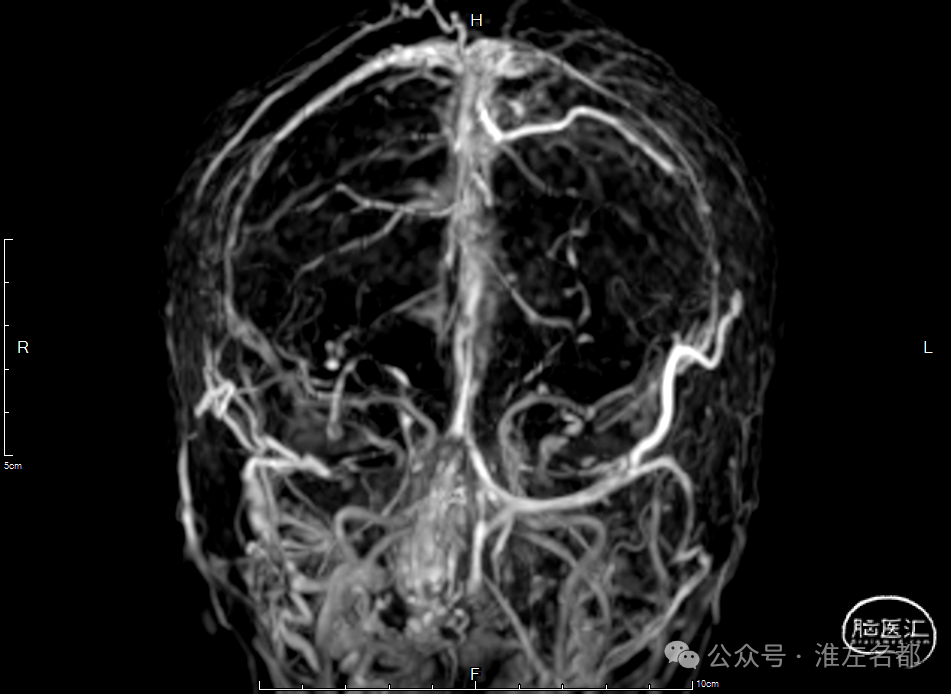

增强MRV:左侧横窦-乙状窦显影纤细;上矢状窦和右侧横窦-乙状窦充盈缺损;脑深部静脉和直窦未见显影。